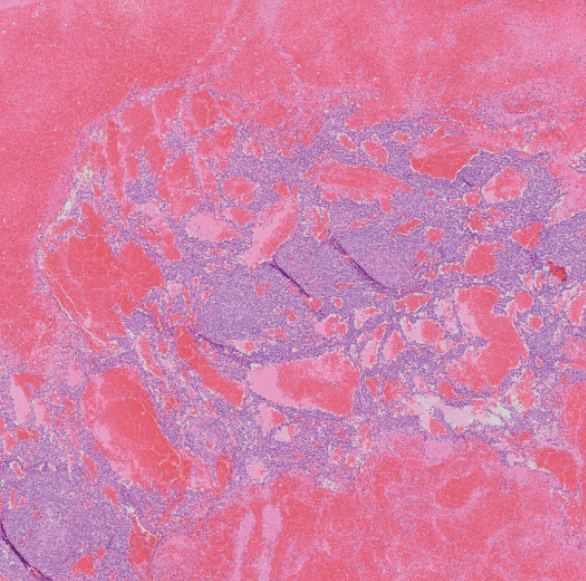

Course notes for hemolymphatic system (spleen, lymph nodes, thymus, and bone marrow).